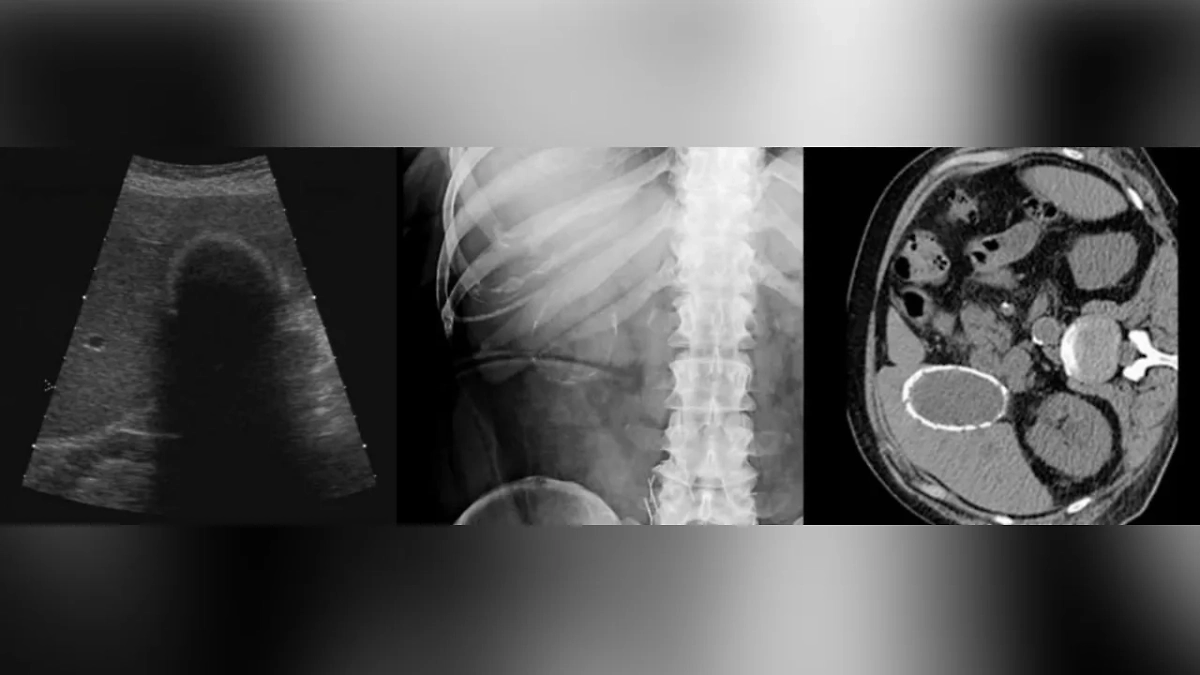

Хирурги Реутовской клинической больницы в Подмосковье прооперировали 46-летнюю женщину с "фарфоровым" жёлчным пузырём — редкой разновидностью холецистита. Пациентка обратилась к медикам с жалобами на тяжесть в правом подреберье. С помощью УЗИ и КТ-исследований врачи диагностировали калькулёзный холецистит — частое заболевание жёлчного пузыря, но редкой разновидности, известной как "фарфоровый" жёлчный пузырь. Его так называют, когда стенки покрыты слоем кальция, что происходит вследствие запущенного холецистита, то есть воспалительного заболевания жёлчного пузыря, и грозит развитием рака, рассказали Life.ru в Минздраве Московской области.

"Во время операции мы выявили жёлчный пузырь необычной твёрдой консистенции, и правда, похожий на фарфоровый: стенку практически невозможно было разрезать скальпелем, в пузырном протоке был фиксированный конкремент. В таких запущенных случаях удалять жёлчный пузырь обязательно, поэтому мы извлекли его лапароскопическим путём", — поделился заведующий хирургическим отделением Реутовской клинической больницы Павел Кудрявцев.